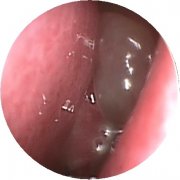

患者信息: 王勇 男 47 症状描述: 鼻塞、 ..[查看全文]